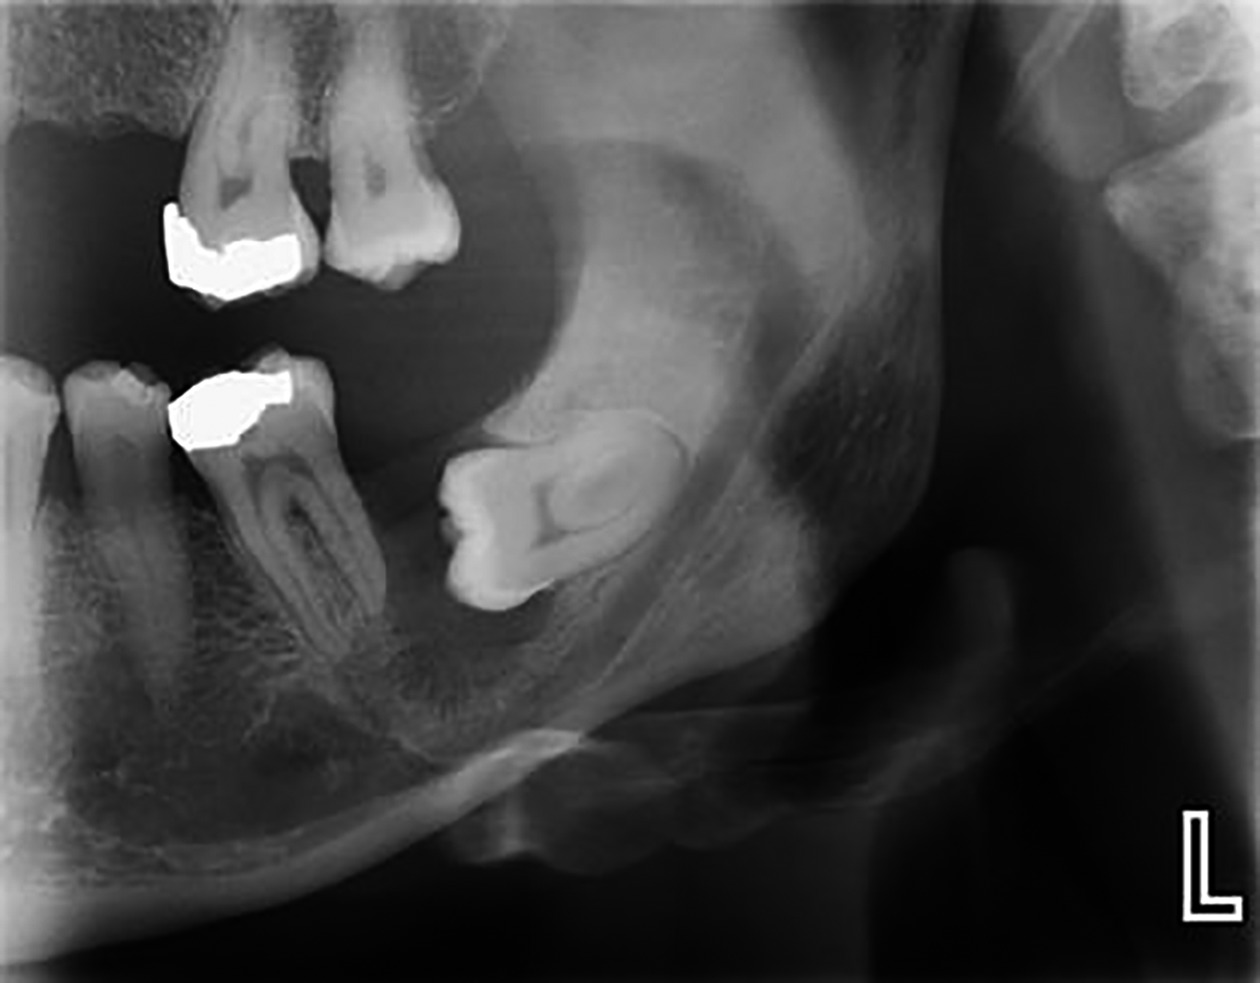

– Nang răng khôn hàm dưới. Trong đó răng khôn ở khá cao gần mỏm vẹt hay lồi cầu, có khi có nhiều ổ, trên X.quang có thể lầm với u men.

+ Giai đoạn thầm lặng: Kéo dài hàng năm, lâm sàng không có gì đặc biệt, khám thấy thiếu một răng, răng sữa vẫn còn tồn tại, lung lay ít hoặc nhiều. X-quang thấy một vùng thấu quang tròn, rõ, quanh một thân răng ngầm ở phía trên. Đôi khi rất khó phân biệt hình ảnh nang hay chỉ là một bọc quanh thân răng giãn ra.

+ Giai đoạn sau : Khi nang đã to, biểu hiện bằng một khối u cứng làm phồng ngách lợi, hoặc cả rãnh mũi – má nhưng vẫn không đau, da- niêm mạc bình thường, nếu vị trí nang phía hàm ếch làm hàm ếch bị phồng. Khi nang tiếp tục to làm xương hàm bị tiêu và mỏng đi, khi đó sờ ở ngách lợi có dấu hiệu bóng bàn. X-quang có hình nang và răng ngầm thân quay vào lòng nang.